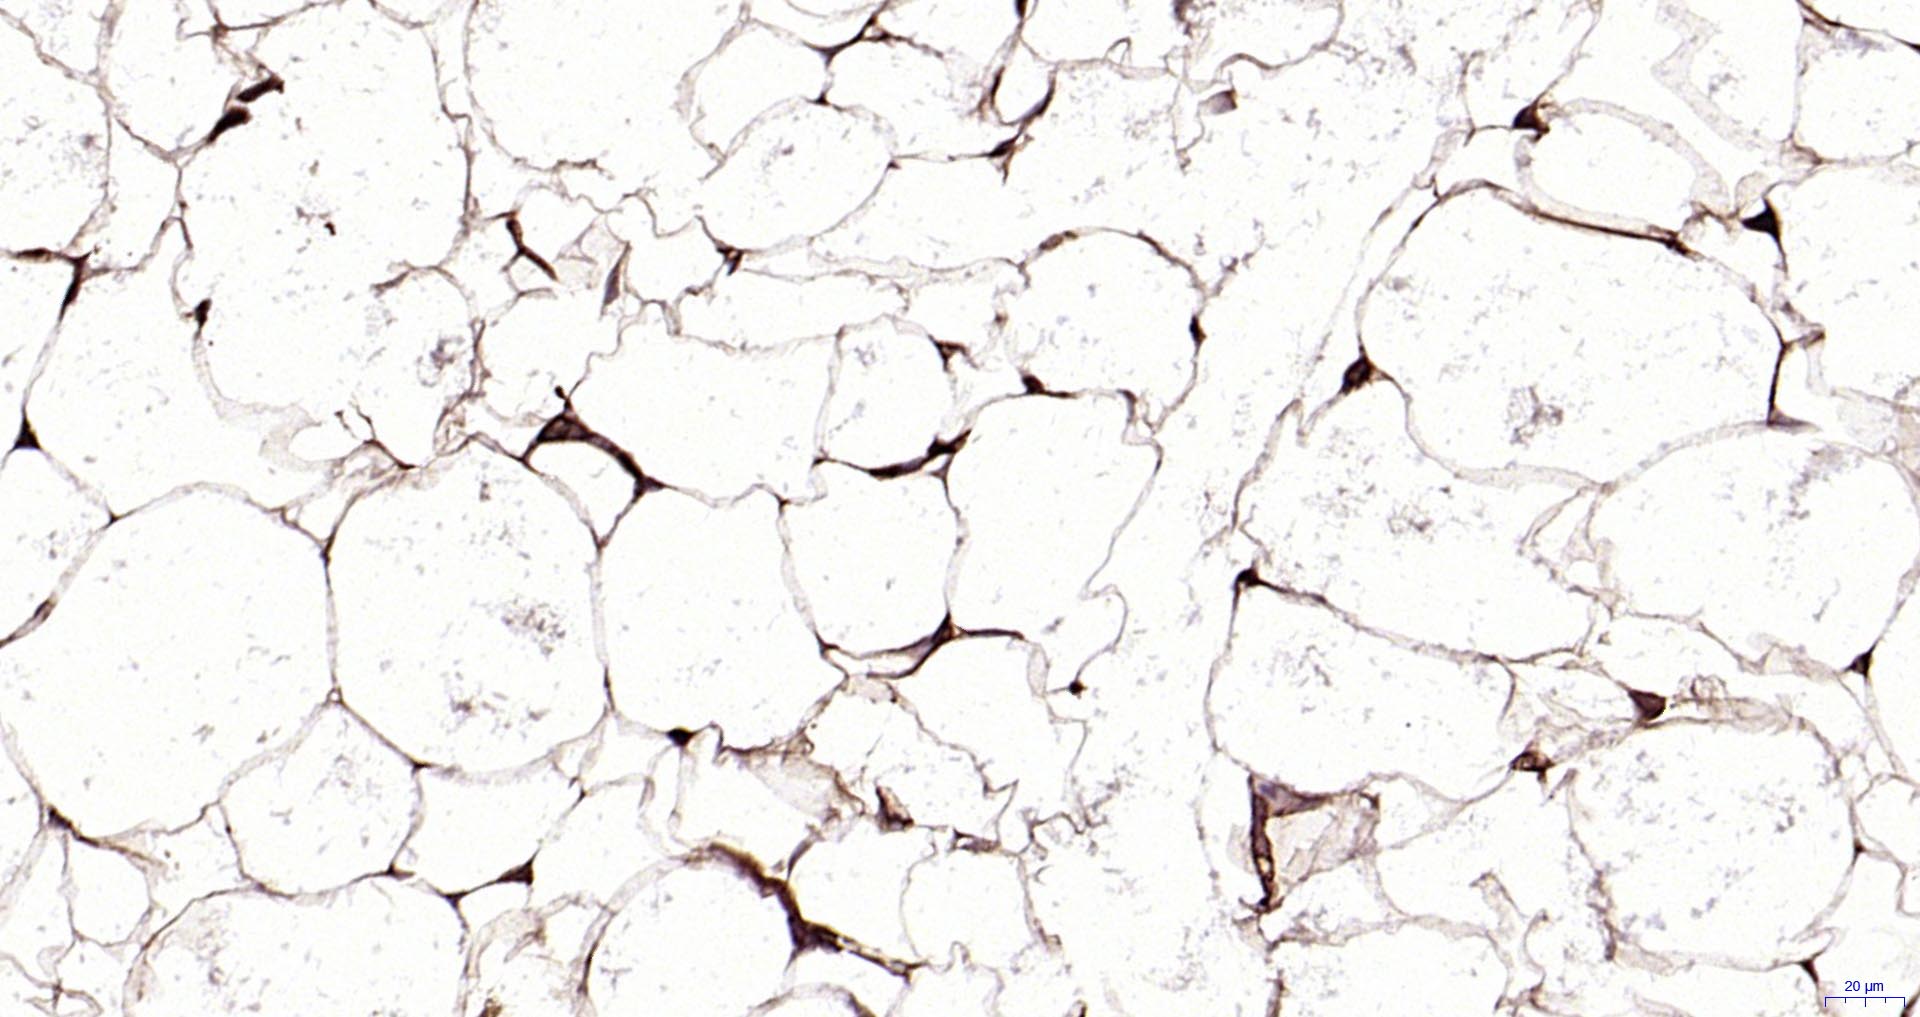

Paraformaldehyde-fixed, paraffin embedded Rat Adipose; Antigen retrieval by boiling in sodium citrate buffer (pH6.0) for 15 min; Antibody incubation with Perilipin A Monoclonal Antibody, Unconjugated(bsm-61033R) at 1:100 overnight at 4°C, followed by conjugation to the SP Kit (Rabbit, SP-0023) and DAB (C-0010) staining.